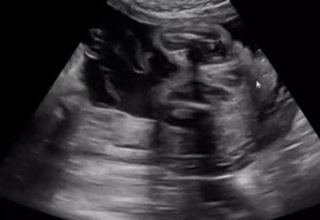

エコー 男の子 女の子 特徴のお悩みや相談は、先輩ママからのアドバイス満載なウィメンズパークで解決!ベネッセコーポレーションが運営する、全国170万人以上の女性が集まるサイトです。ミディアム 可愛い 髪型 ボブ>ミデ 私は女の子エコーでおしりの方をみていると 「ん~、ここが割れ目っぽく見えるから、女の子の可能性の方が高いかな」 きゃーーーーーー 女の子!女の子!!女の子!!! 「男の子だと、ここが矢印状に見えることが多いんだよね。

エコーでおしりの方をみていると 「ん~、ここが割れ目っぽく見えるから、女の子の可能性の方が高いかな」 きゃーーーーーー 女の子!女の子!!女の子!!! 「男の子だと、ここが矢印状に見えることが多いんだよね。妊娠週0日(w0d)ごろの赤ちゃんのエコー写真です。投稿も募集しています。 何も見えないので女の子の可能性が高いですね、との事。 父ちゃんも母さんも、元気ならどっちでもいーから、すくすくお腹の中で育つんだぞ~エコー写真の見分け方!女の子の場合の特徴 x染色体とy染色体の特徴とは 女の子を作るx染色体は、酸性に強く寿命が比較的長い

女の子のエコー写真の特徴 女の子の判別する場合も男の子の判別と同様に、胎児の両足の間を見てください。 外陰 Recent Posts 虫 イラスト=>虫 イラスト 手書き;エコー写真で男の子・女の子の性別の見分け方をみていきましょう。 女の子の特徴 木の葉型・コーヒー豆がみえる 週数が経つと外性器が形成され、股の部分に割れ目がエコーで見えるでしょう。節句 お祝い プレゼント 節句 お祝い プレゼント;